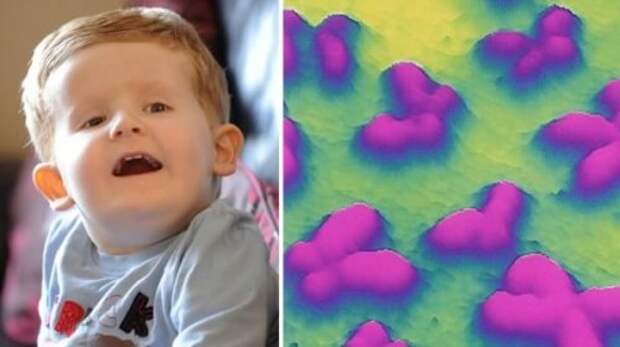

3. Мальчик, который родился с дополнительной цепочкой ДНК

Двухлетний мальчик стал единственным человеком в мире, которому поставлен диагноз дополнительной цепочки в его ДНК.

Храбрый Алфи Клэмп (Alfie Clamp) родился слепым и с тяжёлыми формами инвалидности, что заставило врачей провести ряд тестов.

Тесты показали, что в его седьмой хромосоме есть дополнительная цепочка материала, что никогда раньше не было задокументировано нигде в мире. Врачи были озадачены его состоянием, которое является настолько редким, что у него нет названия. Они также имеют ни малейшего представления, увеличит ли его состояние его продолжительность жизни или уменьшит.

Его родители, Джемма и Ричард Клэмп (Gemma and Richard Clamp), обнаружили что с их сыном что-то не то, только после того как они впервые забрали его домой.

Через несколько дней, он был доставлен в больницу после того, как он перестал дышать, и его губы посинели. Затем, когда ему было шесть недель, врачи обнаружили, что у него была редкая аномалия в ДНК.